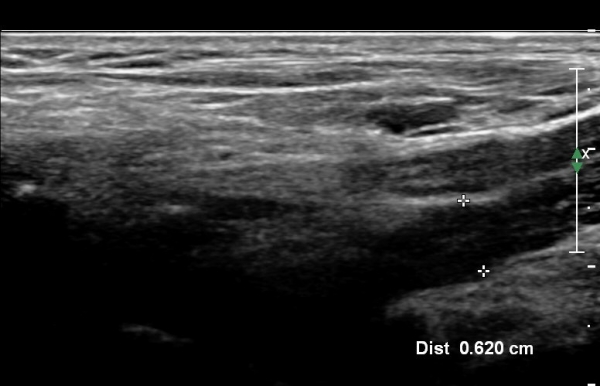

¸ñ ¾Õ ¿ÜÃø¿¡¼­ Á¦5, 6 ½Å°æ±Ù Á¾´Ü¸é°Ë»ç¿¡¼­ Á¦5, 6 ½Å°æ±ÙÀÇ Àú¿¡ÄÚ ºÎÁ¾(4,5mm, 6.5 mm)ÀÌ

°üÂûµÇ°í »çÁø 4,5 ) °ÇÃø(»çÁø 6, 7)(2.4mm, 3.1mm)°ú ºñ±³ÇÏ¸é ¾à 2¹èÀÌ»ó ºÎÁ¾ÀÌ ¶Ñ·ÇÇÔ.